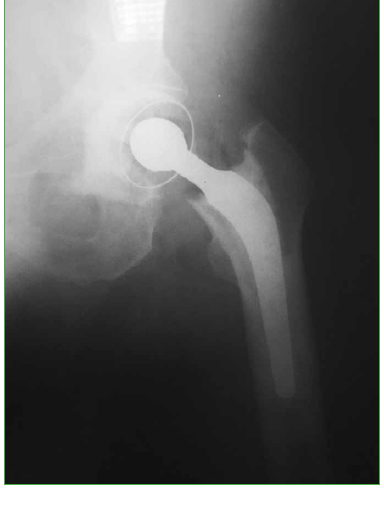

Las fracturas de cadera en pacientes con amputación del miembro homolateral son lesiones infrecuentes que representan un reto para el cirujano ortopédico. Presentamos el caso de un hombre de 63 años con amputación supracondílea izquierda, que sufre una fractura de cuello femoral izquierdo por caída de su propia altura. La colocación apropiada del implante es esencial para obtener buenos resultados clínicos posoperatorios. Para la exposición y la colocación del implante se utilizó un clavo de Steinmann en el trocánter mayor. No se observaron complicaciones clínicas ni radiográficas en un seguimiento de 15 meses. Creemos que el empleo del clavo de Steinmann colocado en una correcta posición es una buena alternativa por considerar para poder controlar el miembro al realizar una artroplastia y así disminuir los riesgos de colocar la prótesis en mala posición y el tiempo quirúrgico.Descargas